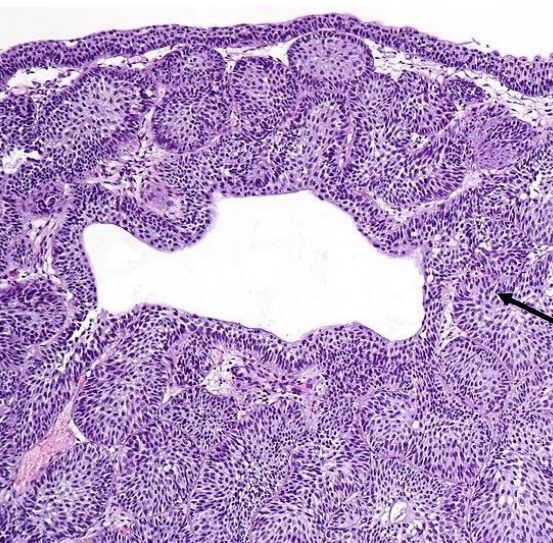

Oh my god, is that cancer?!

Nope, just an inverted urothelial papilloma.

Note how benign and bland the individual cells look. Typically 5-10 cells thick with a smooth stroma-epithelial interface and no stromal reaction.

There may also be some cystic lesions, like cystitis cystica associated with Von Brunn nests.